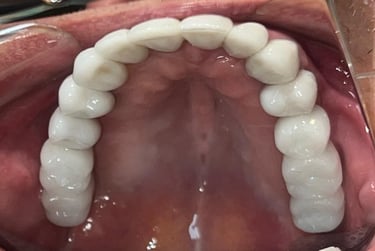

Aspecto Clínico Final - Fotografias originais — nenhuma contém retoques — A cor dos dentes é escolhida de acordo com o gosto e a preferência estética de cada paciente.

Coroas em Dissilicato de Lítio

Todos os caso a seguir estão associadas a clareamento dentário

Caso que demonstra a vantagem da integração de diversas áreas da odontologia, unindo cirurgia, periodontia, prótese e estética para alcançar resultados funcionais e harmônicos.